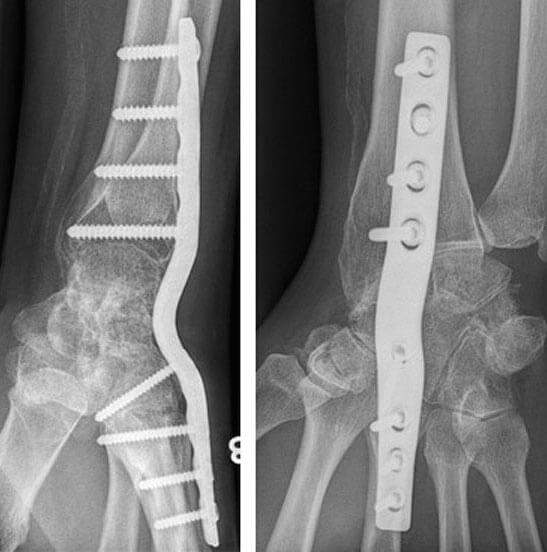

- L’arthrodèse globale du poignet : les articulations du poignet sont toutes fusionnées, et le poignet est alors stabilisé en entier par une plaque d’arthrodèse ou par un autre matériel. Le poignet ne peut alors plus fléchir ni s’incliner. La rotation est conservée.

Arthrodèse totale du poignet (plaque vissée)